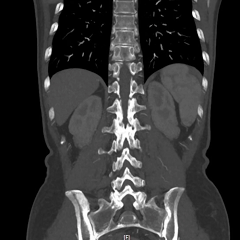

今年8月,李阿姨一家不远千里慕名来到瑞金医院嘉定院区消化道肿瘤多学科联合门诊就诊。就诊当天,来自胃肠外科、血管外科、放射科、病理科、肿瘤科、放疗科等多位专家仔细研读患者的病例及影像学资料,CT检查显示,李阿婆的肚子里竟有直径达30cm的巨大的脂肪肉瘤。肿瘤呈分叶状,填满了腹腔盆腔的间隙,挤压侵犯周围组织器官,病情异常凶险。

与多个腹腔重要血管关系紧密

血管外科冯家烜副主任认为:肿瘤血供丰富,且累及肠系膜上血管等多个重要血管,术中出血风险高,可预先DSA行肿瘤供血血管栓塞,减少术中出血;对于受侵血管,可切除后行血管重建。有了多学科保驾护航,瑞金医院副院长、嘉定院区普外科执行主任赵任教授表示:这个患者的手术虽然难度极高这个手术虽然难度极高,但是仍有根治性手术切除的机会!李阿姨一家看到希望的曙光,当即决定,为生命勇敢一搏!

术中发现,患者肿瘤不仅体积十分巨大,还侵犯包绕了肠系膜上静脉等多个腹腔重要血管!赵任教授精心剥除肿瘤,尽可能保留了小肠等器官血供,对于受侵严重的肠系膜上静脉,冯家烜主任为患者进行了血管修补重建。手术历经四个半小时,团队将重达4kg、直径近30厘米的肿瘤连同受侵部分小肠完整切除!